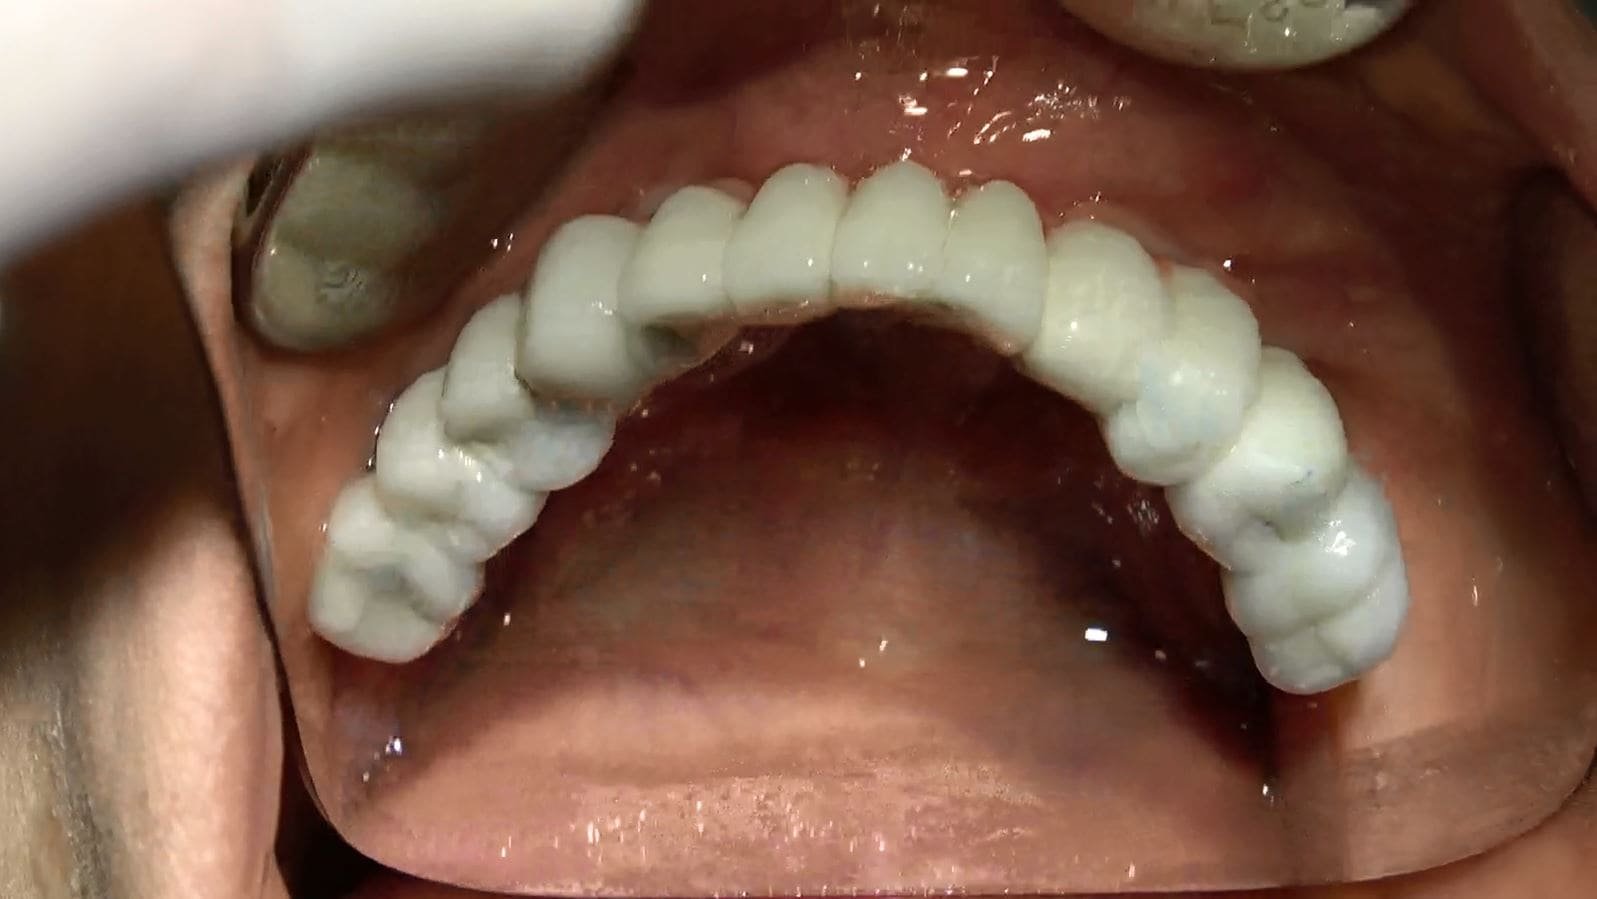

• Il video documenta ogni fase dell’intervento, dalla progettazione personalizzata della griglia sottoperiostea all’applicazione dei singoli impianti e, infine, alla realizzazione di una protesi dentale a carico immediato.

• Accompagniamo il video con una galleria fotografica dettagliata che cattura ogni fase del processo e i risultati finali sorprendenti.

• Dopo un periodo di circa 6 mesi, quando l’integrazione degli impianti è completa, la protesi provvisoria può essere sostituita con una protesi dentale fissa definitiva in ceramica, composta da 14 denti.

Passati 6 mesi di osteointegrazione si sostituisce protesi fisse provvisorie con protesi fisse in ceramica definitiva 14 denti